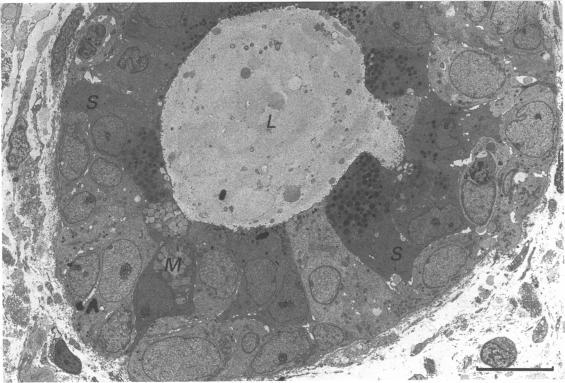

Twenty two mid-trimester human fetal tracheae were processed for light microscopy and scanning, transmission and freeze-fracture replication electron microscopy. The tracheal pseudostratified columnar epithelium was found to be composed of four cell types: ciliated in various stages of development, non-ciliated, basal and degenerating cells. The ratio of ciliated to non-ciliated cells was approximately one-to-one. The non-ciliated cells were of two morphological sub-types. Of these, the vast majority contained characteristic secretory granules, approximately 0.5 microns diameter, found in abundance within the apical region of the cell cytoplasm. The second sub-type of the non-ciliated cell, the well differentiated goblet cell, was observed very infrequently. The relatively large number of non-ciliated cells in the fetal tracheal epithelium suggests a transition stage to the adult where the ratio of ciliated to non-ciliated cells is near 5-to-1. The nature of the first type of the non-ciliated cells, which have not been studied in depth previously, remains obscure. Their probable secretory function is discussed and comparisons are made with previously reported cell types showing similar features, in fetal or adult material from the distal airways of animal and human tissues. Approximately 15 to 20% of the epithelial cells show signs of degeneration. The probable causes of this degenerative process are discussed. Other cell types such as brush cells, endocrine and wandering lymphocytes were not observed. Well-differentiated muco-serous glands were observed within the tela submucosa.

对22个孕中期人胎儿气管进行了处理,用于光学显微镜检查以及扫描电子显微镜、透射电子显微镜和冷冻断裂复型电子显微镜检查。发现气管假复层柱状上皮由四种细胞类型组成:处于不同发育阶段的纤毛细胞、非纤毛细胞、基底细胞和退化细胞。纤毛细胞与非纤毛细胞的比例约为1:1。非纤毛细胞有两种形态亚型。其中,绝大多数含有特征性分泌颗粒,直径约0.5微米,大量存在于细胞质顶端区域。非纤毛细胞的第二种亚型,即分化良好的杯状细胞,很少观察到。胎儿气管上皮中相对大量的非纤毛细胞表明其处于向成人阶段的过渡阶段,成人纤毛细胞与非纤毛细胞的比例接近5:1。此前未深入研究的第一种非纤毛细胞的性质仍不清楚。讨论了它们可能的分泌功能,并与动物和人类组织远端气道的胎儿或成人材料中先前报道的具有相似特征的细胞类型进行了比较。约15%至20%的上皮细胞显示出退化迹象。讨论了这种退化过程的可能原因。未观察到其他细胞类型,如刷状细胞、内分泌细胞和游走淋巴细胞。在黏膜下层观察到分化良好的黏液浆液腺。